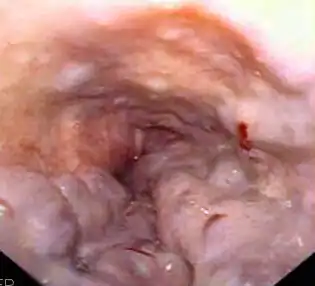

| Imagem endoscópica de varizes esofágicas com manchas vermelhas | |

Varizes esofágicas são dilatações das veias do esôfago. São relacionadas em geral com a cirrosee a esquistossomose e outras doenças que provocam hipertensão da veia porta e podem se romper e provocar hemorragias renais.